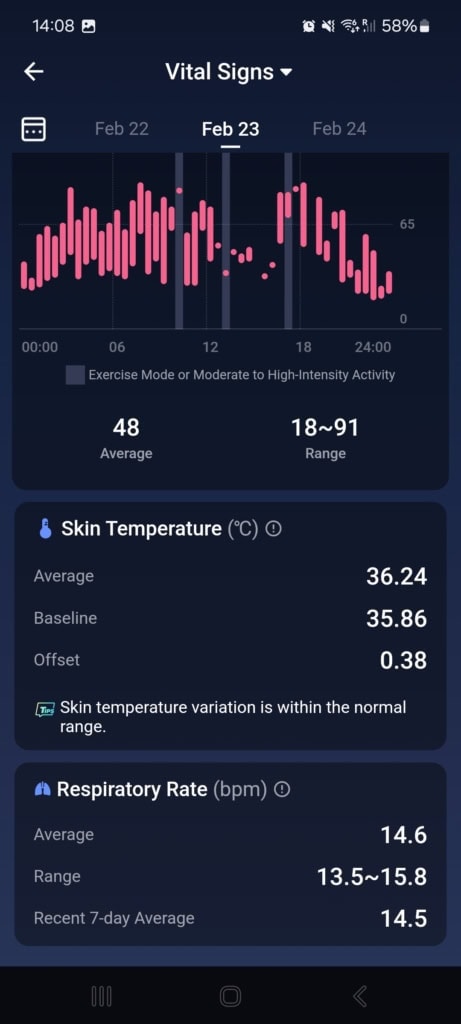

Stan funkcji życiowych (Znaki życia)

W tej części aplikacji dowiesz się o całodziennych wahaniach tętna i jego zmienności, nasyceniu krwi tlenem, częstotliwości oddechów podczas snu i temperaturze snu. Aplikacja porównuje wszystkie te dane z twoją własną referencją z ostatnich 7 do 30 dni oraz z referencyjnymi wartościami medycznymi. Gdy tylko w ciągu dnia lub nocy osiągniesz wartości, które nie mieszczą się w referencyjnych granicach, aplikacja cię o tym poinformuje.

Najczęściej spotykałem się z wyraźnym spadkiem zmienności tętna i wzrostem samego tętna. Te wahania pojawiały się czasem podczas snu, aktywności sportowej lub w przypadkowych sytuacjach, o których nie miałem pojęcia. Mimo że doceniam ten kompleksowy wgląd w moje funkcje życiowe, brakowało mi podczas testowania kontekstu. Funkcja oferuje jedynie wartości i spostrzeżenia, że coś jest nie tak. Nie znalazłem w aplikacji żadnych wskazówek dotyczących możliwych przyczyn ani rekomendacji działań, które mogłyby pomóc przywrócić stan do normy.

Mimo że nietypowe wartości nie mają jasnego kontekstu, aplikacja zwraca na nie uwagę i pyta, co mogło być ich przyczyną (spożycie alkoholu, infekcja, kofeina i inne). W moim przypadku działało to idealnie. Popełniłem błąd dietetyczny, przez który dostałem gorączki i problemów trawiennych. Mój ogólny stan znacznie się pogorszył, co objawiło się wyraźnym spadkiem jakości snu, obniżoną zmiennością tętna i podwyższoną temperaturą ciała. Wszystkie te zmiany zostały przez pierścień i aplikację trafnie rozpoznane i ocenione. Po kilku dniach mój stan się poprawił – również to zostało odnotowane i odpowiednio skomentowane.